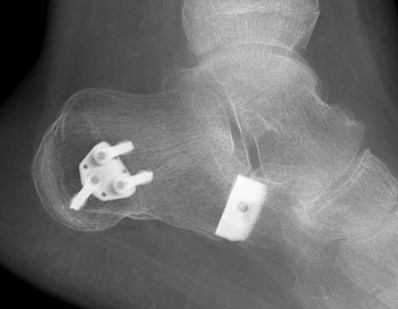

Evans Calcaneal Lengthening Osteotomy

Evans Osteotomy + MT Osteotomy + FDL transferEvans Osteotomy + MT Osteotomy + FDL transfer Oblique

Technique

Incision over anterolateral distal calcaneum

- sural nerve retracted plantar

- P longus retracted plantar

- identify CCJ

- Z lengthen P brevis

- homan retractor in sinus tarsi (between middle and anterior facets)

- homan retractor inferior calcaneum

- K wire into CCJ to prevent subluxation

Opening wedge osteotomy

- 1.5cm proximal to CCJ

- between middle and anterior facets medially

- begin with saw, complete with osteotome

- open 1 cm

- triangular / trapezoidal bone graft (allograft, iliac crest / mid fibular autograft)

- fixation with plate / staple / screw

+/- tendoachilles lengthening

+/- modified Kidner procedure (imbricate spring ligament, Tibialis posterior advancement)